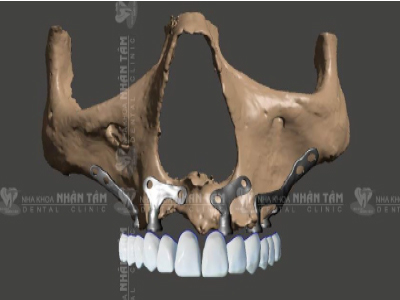

Dời dây thần kinh hàm dưới và cấy ghép Implant xương gò má hàm trên cho bệnh nhân thiếu răng bẩm sinh

Bệnh nhân N.T.K.H - bị thiếu răng bẩm sinh nên xương hàm không phát triển, cộng với việc đeo hàm giả từ khi còn trẻ, khiến cho xương hàm trên và dưới bị tiêu trầm trọng. Để phục hồi chỉ còn một giải pháp duy nhất là thực hiện đồng thời hai kỹ thuật: dời dây thần kinh, cấy ghép Implant để phục hồi răng hàm dưới và cấy ghép Implant xương gò má để phục hồi răng hàm trên.

Dời dây thần kinh hàm dưới và cấy ghép Implant xương gò má hàm trên cho bệnh nhân không răng bẩm sinh

Bệnh nhân B.Q.L mắc hội chứng loạn sản ngoại bì, không có răng từ lúc mới sinh, dẫn đến xương hàm không phát triển, nướu teo và mỏng, xương hàm trên tiêu chỉ còn sát nền mũi, xương hàm dưới còn lại rất ít, chỉ cách dây thần kinh 1 mm. Ts.Bs Võ Văn Nhân cũng áp dụng đồng thời 2 kỹ thuật: phẫu thuật dời thần kinh để trồng răng hàm dưới và Cấy ghép Implant xương gò má để trồng răng hàm trên.